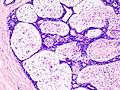

Histopathologic image of breast fibroadenoma showing proliferation of intralobular stroma compressing and distorting the epithelium. H&E stain.

Fibroadenoma of the breast is a benign tumor composed of a biphasic proliferation of both stromal and epithelial components that can be arranged in two growth patterns: pericanalicular (stromal proliferation around epithelial structures) and intracanalicular (stromal proliferation compressing the epithelial structures into clefts).

These tumors characteristically display hypovascular stroma compared to malignant neoplasms.[2][5][8] Furthermore, the epithelial proliferation appears in a single terminal ductal unit and describes duct-like spaces surrounded by a fibroblastic stroma. The basement membrane is intact.[11]